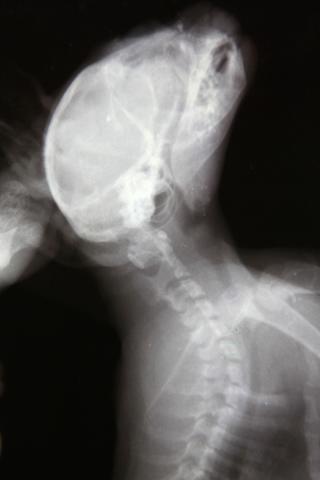

Здравствуйте. У меня приёмный котёнок-подобрашка. Был подобран на улице девушкой волонтёром в первых числах августа, примерно в 2-х месячном возрасте. У котенка расстройства координции. Светлана сделала котёнку рентген, на котором выявлено повреждение 1 шейного позвонка. Первично было назначено: пирацетам, ловетта, фуросемид; далее добавлены мильгамма, преднизолон. Переназначение от другого врача: Мильгама, Нейромедин 0,3*2р/д 15 дней. Курс Нейромедина проведён уже 2-х кратно. Улучшения незначительные, недолговременные. Нарушения координации выражются в треморе головы при малейшем возбуждении (бьётся носом об тарелку, когда кушает), дискоординация движения ног при ходьбе- спина не выпрямляется, задние ноги находят на передние- заваливается на бок, плохо развиты задние конечности, передние контролирует лучше. Планируем в ближайшее время МРТ. Какой отдел нам делать, посоветуйте. Буду рада любой информативной помощи. Спасибо! Это наши снимки.

Извините, как-то пропустила вашу тему. Снимки нечеткие, рассмотреть масштаб трагедии я по ним не могу, тем более снимки сделаны только в сагиттальной проекции, а хотелось бы увидеть и фронтальную.

Tella, Михаил Александрович! Очень благодарна вам за содержательные ответы!!!! Уточню, так как снимки выложены, действительно, не в очень хорошем качестве. Врач, наблюдающий Севу и назначивший нам последнее лечение увидел на снимке трещину на атланте. Где порекомендуете провести нам подобное исследование и возможную операцию? Специализируетесь-ли вы в этом направлении?

Лично я специализируюсь именно на этом направлении. Но про трещину на атланте - как то очень сомнительно. В таком, как у Вас, возрасте кости не ломаются, а, скорее, гнуться. И кости позвонков очень эластичны. Да и трещина если и есть, то что плохого? Трещина - это перелом без смещения. А раз нет смещния то в чем может быть проблема?